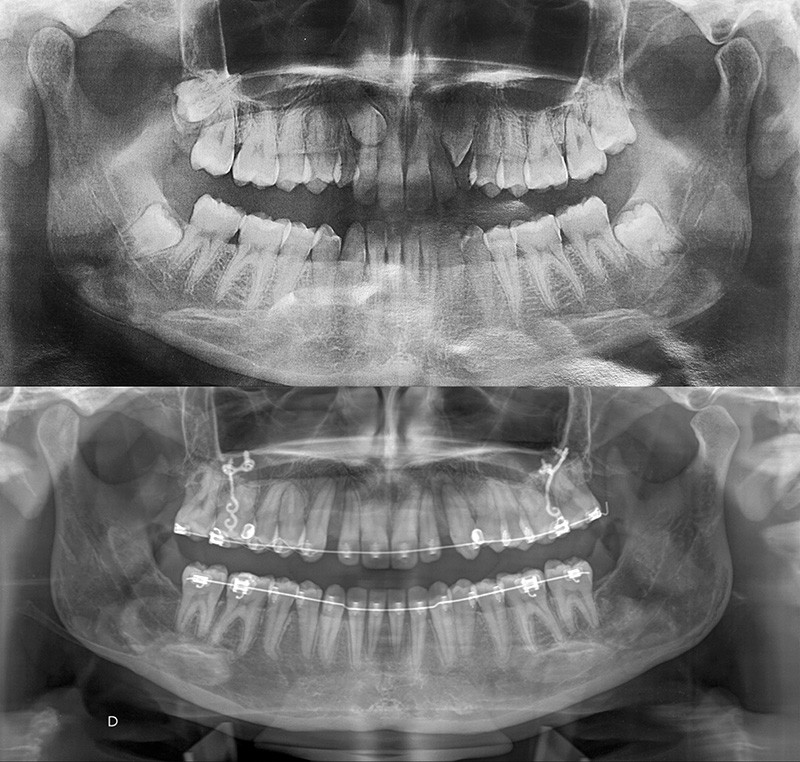

Aline se présente à la consultation pour une demande esthétique concernant ses deux canines lactéales qu’elle trouve trop petites et trop blanches (fig. 1a). Elle présente une classe II squelettique légère sur un schéma méso-divergent. D’un point de vue dentaire, une supraclusion est associée à une classe II d’Angle complète à gauche et de 4 mm à droite. Les canines maxillaires sont incluses (une vestibulaire et une palatine), avec persistance de leurs dents lactéales sur l’arcade (fig. 1b-h).

Dans un premier temps, des attaches bidimensionnelles (20/25 antérieures et 22/28 postérieures en Roth) sont collées aux deux arcades. L’alignement-nivellement est initié par des 0.014 Niti. Des plaques d’ancrages osseuses…